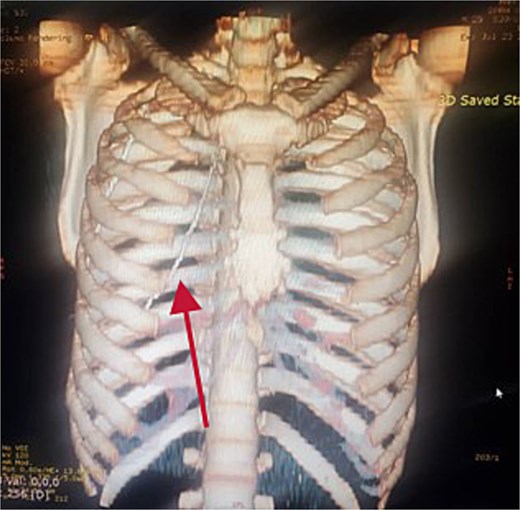

Further evaluation with chest ultrasound and computed tomography (CT) thorax, performed 48 h later, confirmed the guide wire’s position (Figs 3 and 4). The imaging studies demonstrated that the tail end of the guide wire was lodged in the right subclavian vein, while the remainder was situated in the pleural space of the right hemithorax. Notably, the guide wire was in contact with the 7th rib along the anterior and mid-axillary line. Additionally, a moderate right hemothorax had developed.